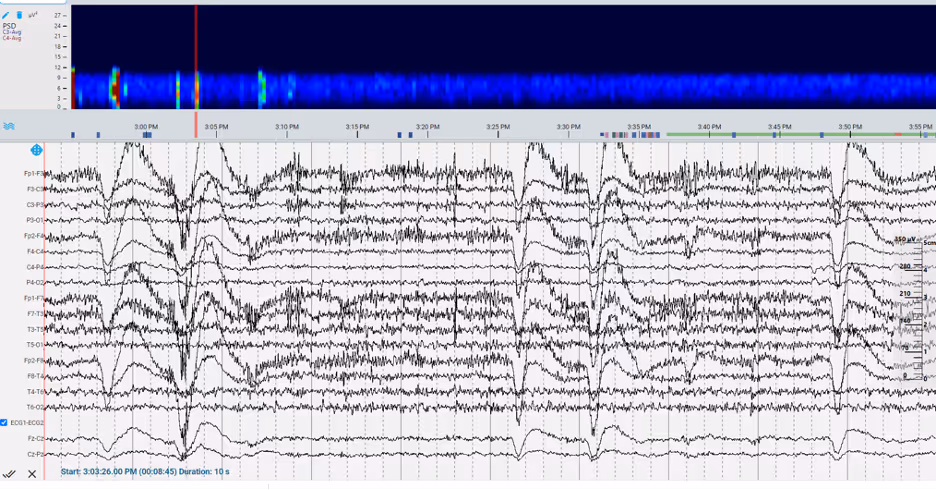

EEG Trends in Raw Data

Trends in Frequency

The EEG signal is composed of multiple waves that can be decomposed into set frequency bands (i.e., delta, theta, alpha, beta, and gamma activity). Monitoring trends in frequencies provides a visualization of the power for each of the frequency bands over a period of time. Clinicians reviewing trends in frequency bands can screen for acute state changes, as well as suppression activity. These trend analyses can also determine possible seizure patterns by identifying abrupt changes in power across a range of frequencies.